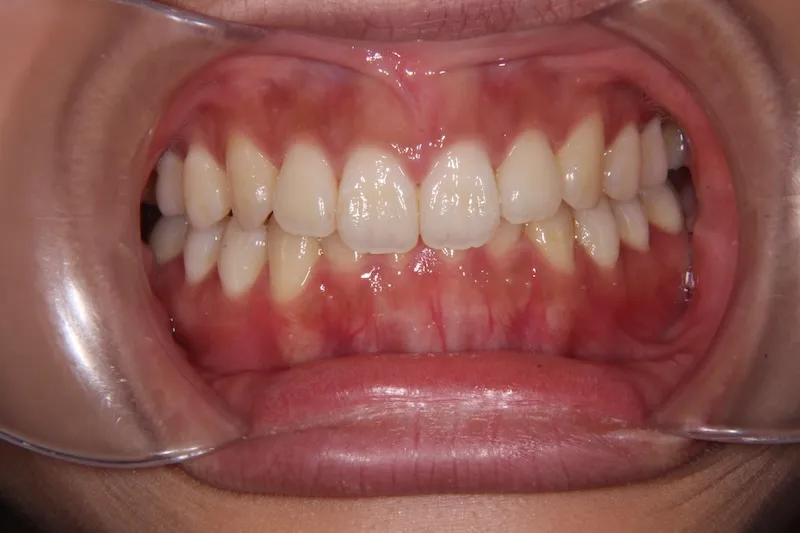

【大人の矯正】出っ歯・開咬・前歯で物が噛みちぎれない・滑舌が悪い・19歳女性【N.T様】

初診時年齢 19~29歳 (女性) 主訴 前歯で物が噛みちぎれない

診断名 開咬・上顎前突 装置名

前歯で物が噛みちぎれないを主訴に来院された患者様です。

非抜歯で、オリジナルリンガルアーチと歯科矯正用アンカースクリューを用いて治療しました。

治療回数15回、1年の治療期間で矯正治療を終了しました。

主訴が改善され、ご満足頂きました。